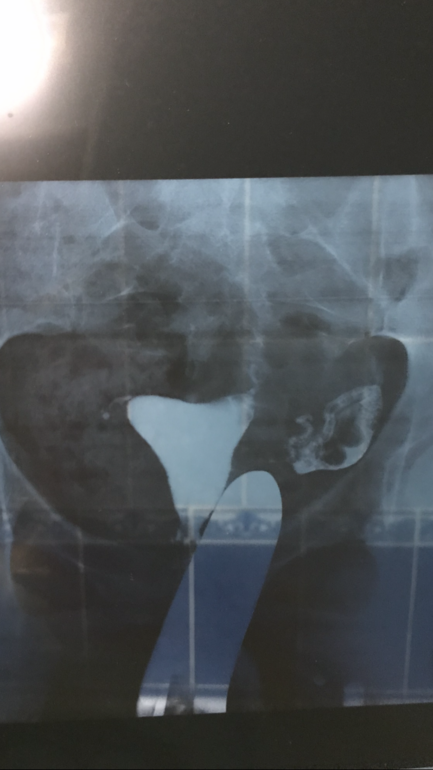

Судя по всему у Вас проходима только одна труба (левая), с другой трубы жидкость не вытекла, увы...

Ну, врачу виднее. Но, жидкость прошла, а это уже хорошо, значит все не так плохо. Говорят даже, что гсг даже может маленькие спайки разорвать. По статистике в первые 3 мес после гсг многие беременеют. Я через 2 цикла забеременела, чего и Вам желаю)

Если жидкость прошла, то и сперма пройдет. Спайки могут быть и внутри, просто незначительные. Советую Вам обратится с этим снимком ещё а нескольким специалистам, мало ли, а то вдруг этот врач не правильно интерпретировал или хочет заработать на Вас деньги назначив лечение...

Сперма может пройдти , но оплодотворённая яйцеклетка уже вряд ли сможет . Посоветуйтесь с другими врачами . И удачи вам .

Это 1-й снимок

это 2-й